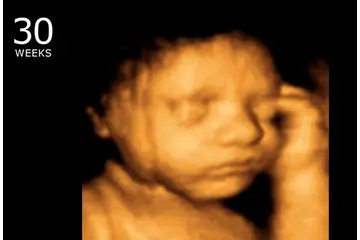

| 15 haftalık gebelik, hamileliğin ikinci trimesterine geçişin başlangıcını temsil eder. Bu dönem, hem anne hem de fetus için birçok fiziksel ve duygusal değişikliği beraberinde getirir. Bu makalede, 15 haftalık gebelikteki gelişmeler, fetal gelişim, anne sağlığı ve takip edilmesi gereken önemli noktalar ele alınacaktır. Fetal Gelişim 15. haftada, fetüs birçok önemli gelişim evresinden geçmiştir. Bu dönemdeki temel özellikler şunlardır: